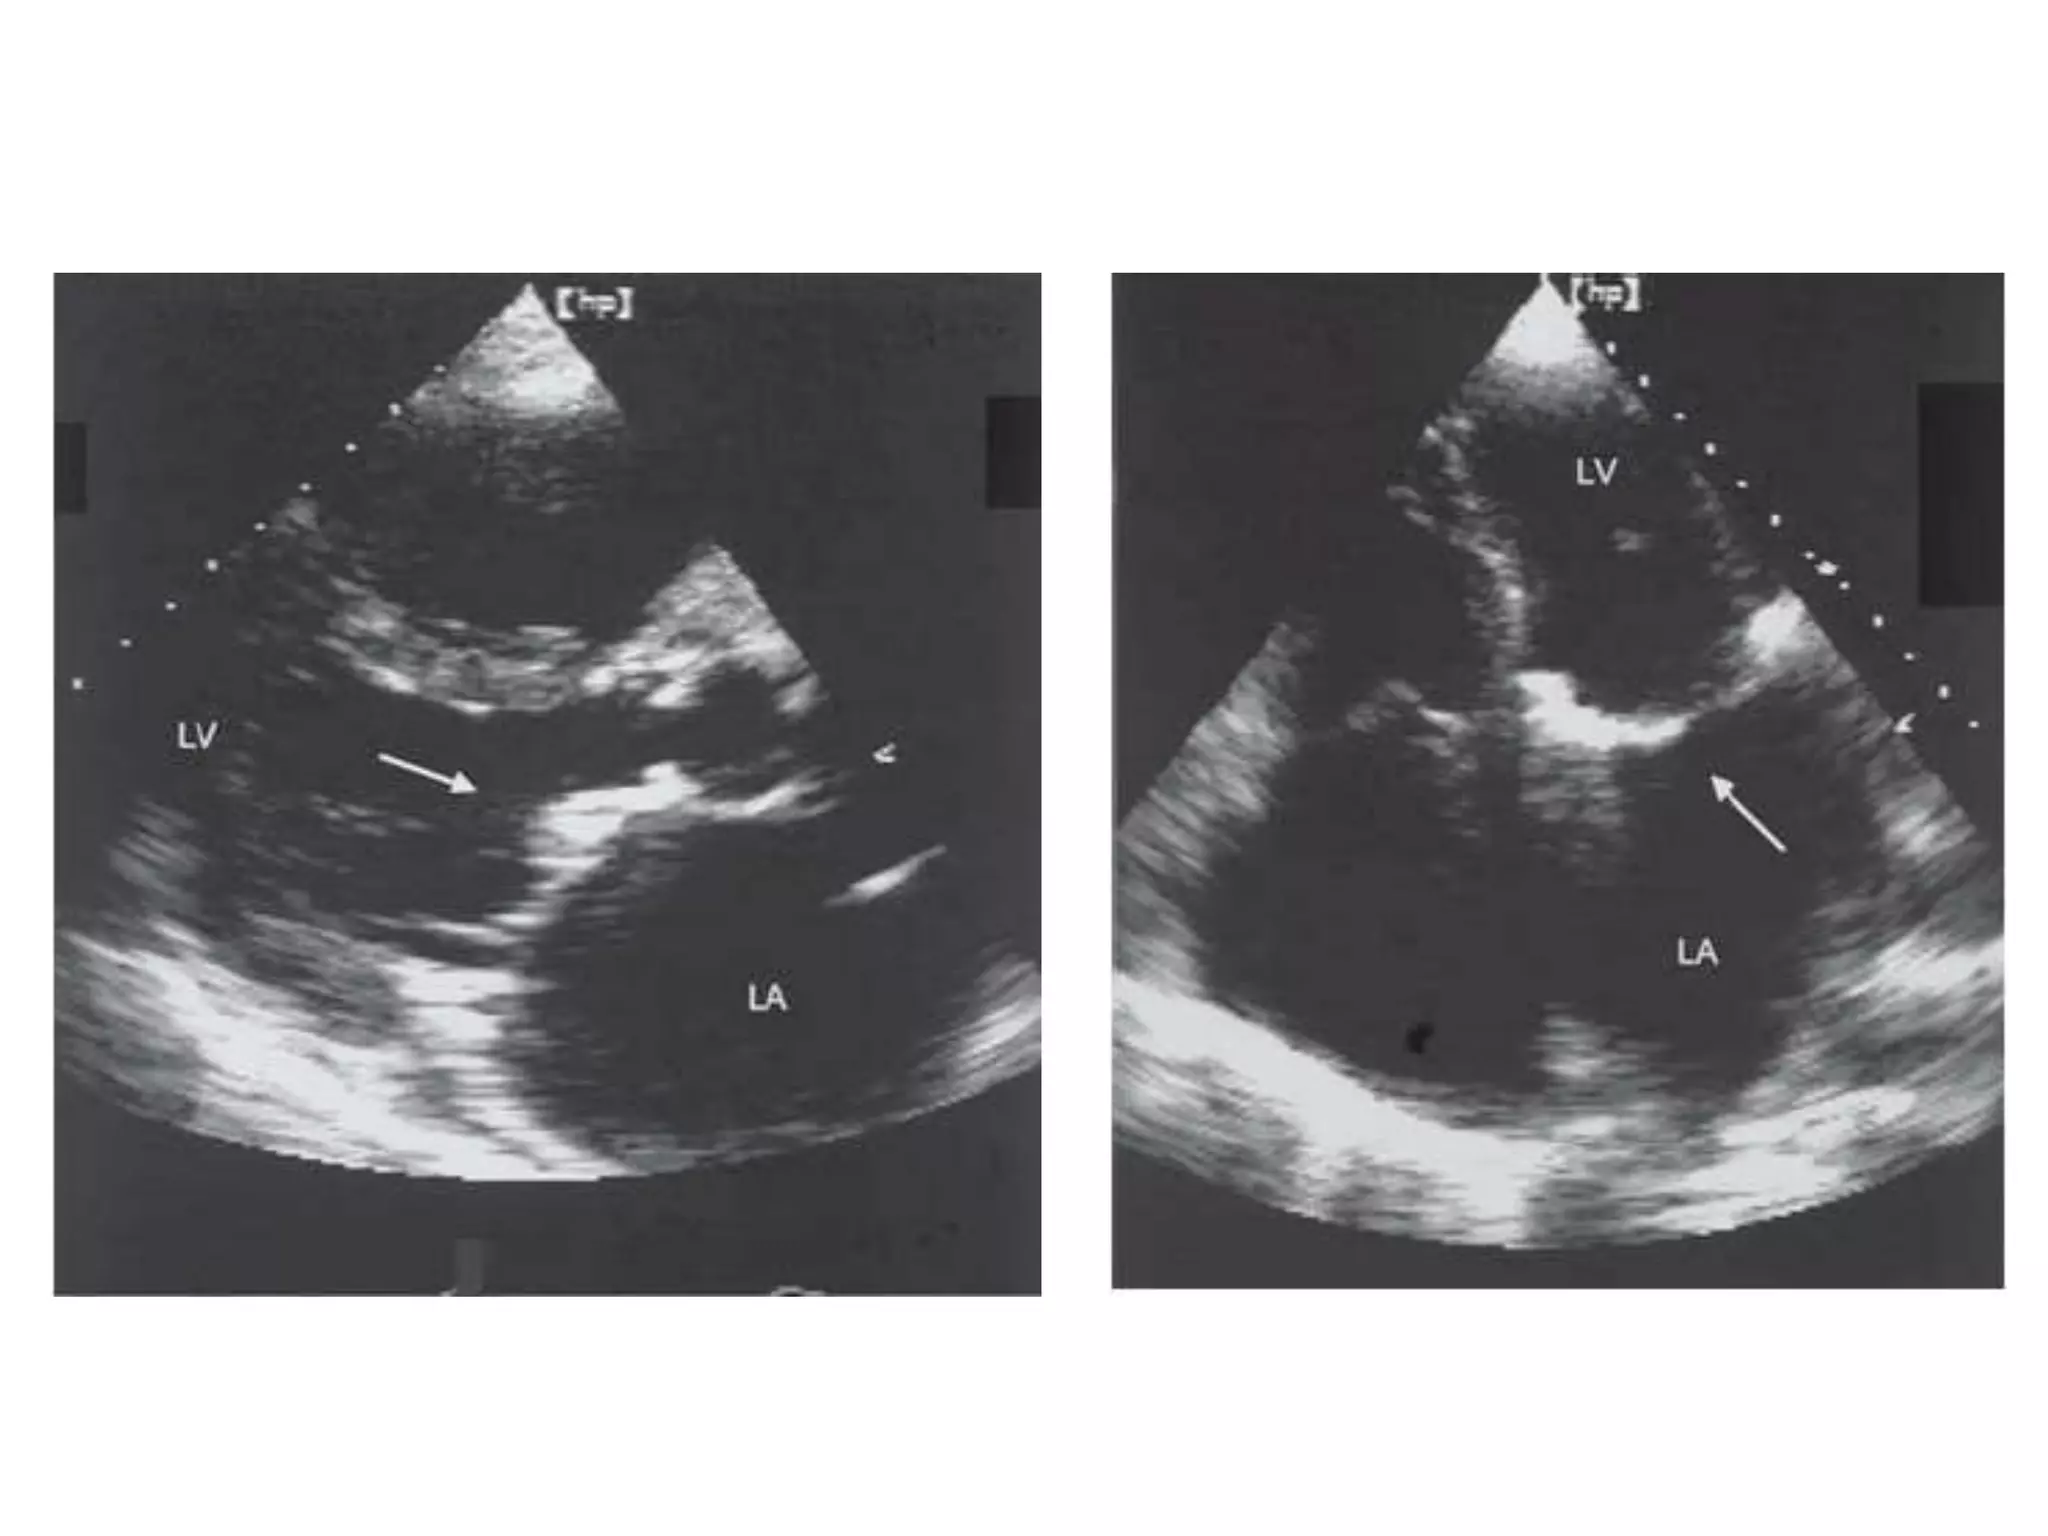

INFECTIVE ENDOCARDITIS